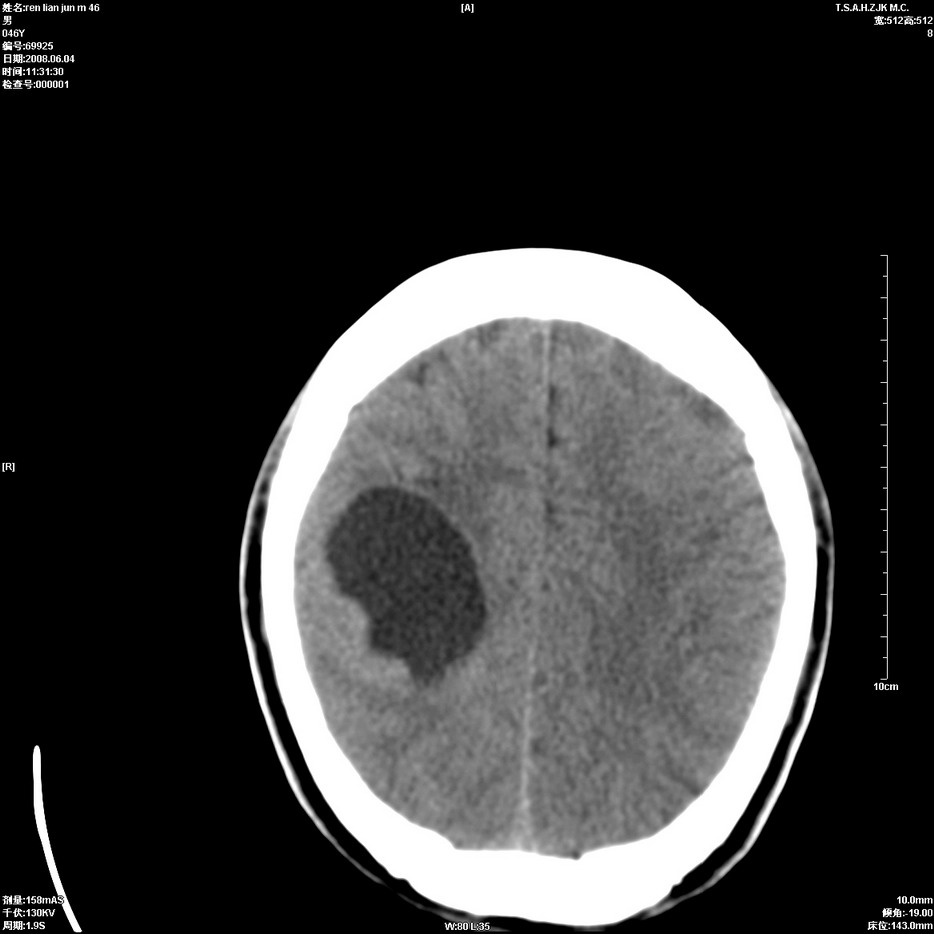

以下是引用qiu999在2008-6-5 17:14:00的发言:[br]考虑右肺中心型肺癌.颅内应做增强检查.

以下是引用形影不离在2008-6-5 19:18:00的发言:[br]右肺中心型肺癌并纵隔及左侧腋窝淋巴结转移,颅内应做增强检查。

以下是引用杀毒软件在2008-6-5 18:33:00的发言:[br]支持考虑右肺中心型肺癌,颅内病变是不是转移,不好说